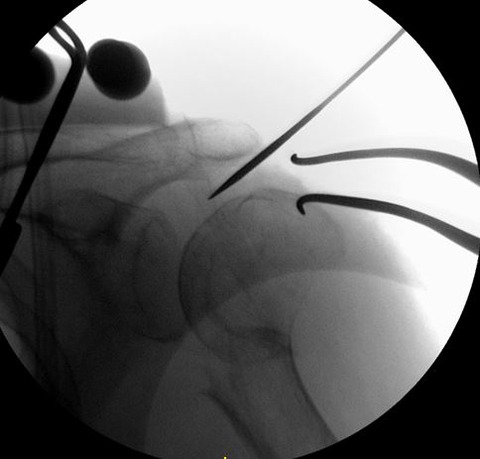

髄内釘のエントリーポイントを至適にするためには、転位した上腕骨頭を整復する必要があります。私は2.4 K-wireを肩峰外側から上腕骨頭に2本刺入して、これをjoy-stickにして整復します。

まず、1本目の2.4 K-wireを肩峰下に沿ってできるだけ上腕骨頭内側に進めます。この際、どうしても肩峰の外側が邪魔になるのですが、ある程度仕方ありません。

1本目の2.4 K-wireをできるだけ上腕骨頭内側に刺入して、これをjoy-stickにして整復します。しかし1本では整復力が弱いので2本目を刺入して、更に強力に整復を行います。

2本のK-wireをjoy-stickにして思いっきり整復します。上腕骨頭を内転位に保ちながら、上腕骨頭の頂点からガイドワイヤーを刺入します。

K-wireで上腕骨頭を内転位に整復位を保っておかないと腱板に牽引されて外転転位してしまい、髄内釘のエントリーポイントがかなり大結節寄りになってしまいます。

髄内釘のエントリーポイントが大結節寄りになりすぎると、ネイル挿入時に骨折を併発したり、髄内釘の固定力が落ちるので注意が必要です。この手術で一番重要なポイントだと思います。